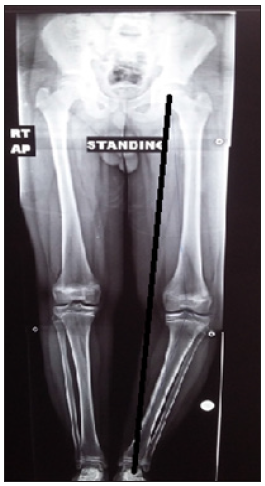

A detailed history taking, clinical examination of the patient and the affected limb was done to exclude the presence of skeletal dysplasia, short stature and leg length discrepancy (Figure). The limb was examined for range of motion, ligamentous laxity, neurovascular status and skin condition. Radiographic examination included long standing X- ray films and CT scanogram to evaluate the mechanical axis and limb length (Figure 1). Short films for the tibia and femur on both sides were also obtained.

Figure 1: Preoperative long standing x ray film of lower limb of a 14-year-old boy showing left adolescent blounts with medial axis deviation (black line).